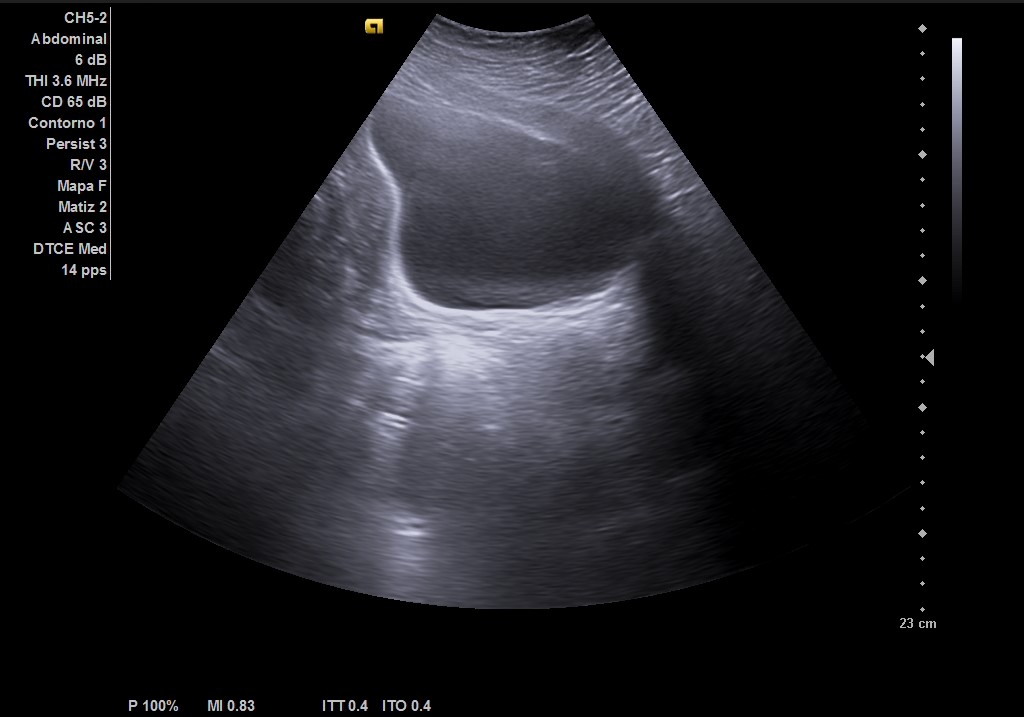

Ecografía abdominal: masa heterogénea de 10 x 10 cm dependiente de útero con vascularización periférica. No se observa la vejiga al estar repleccionada y desplazada por dicha masa. Se vuelve a hacer ecografía con vejiga llena y se observa cómo deforma la pared por efecto masa. Vejiga sin litiasis en su interior, no globo vesical.

El diagnóstico diferencial de la metroragia se realizaría con una gestación incipiente, pólipo endometrial, endometriosis. Y el de la masa con un globo vesical.